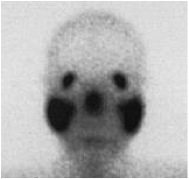

As a result of that, the patient might need to go through a long list of investigations. After assessing this patient and reviewed the CT images; we found that there was significant discordant between the alarming CT features and the totally asymptomatic clinical status. This discordance made metastatic calcification the most likely diagnosis. Bone scan was then arranged(picture 4) which showed intense uptakes in patient’s both lungs that almost equal to the uptake of bone.

For our patient, we did not resume the empirical TB treatment. His PET scan (picture 5) demonstrated active uptake in BHL and also the classical Panda sign compatible with sarcoidosis